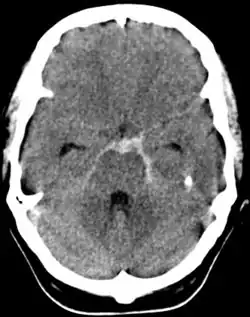

Subarachnoidální krvácení

Subarachnoidální krvácení je krev mezi pavučnicí a vlastní mozkovou tkání. Klinický obraz je často zastřen dominujícím poraněním. Je jím meningeální syndrom, vazospazmus (prevence: blokátory kalciových kanálů či opakovaná lumbální punkce). Prognóza je dobrá. Komplikací jsou vazospazmy a komunikující hyporesorpční hydrocefalus.[2]